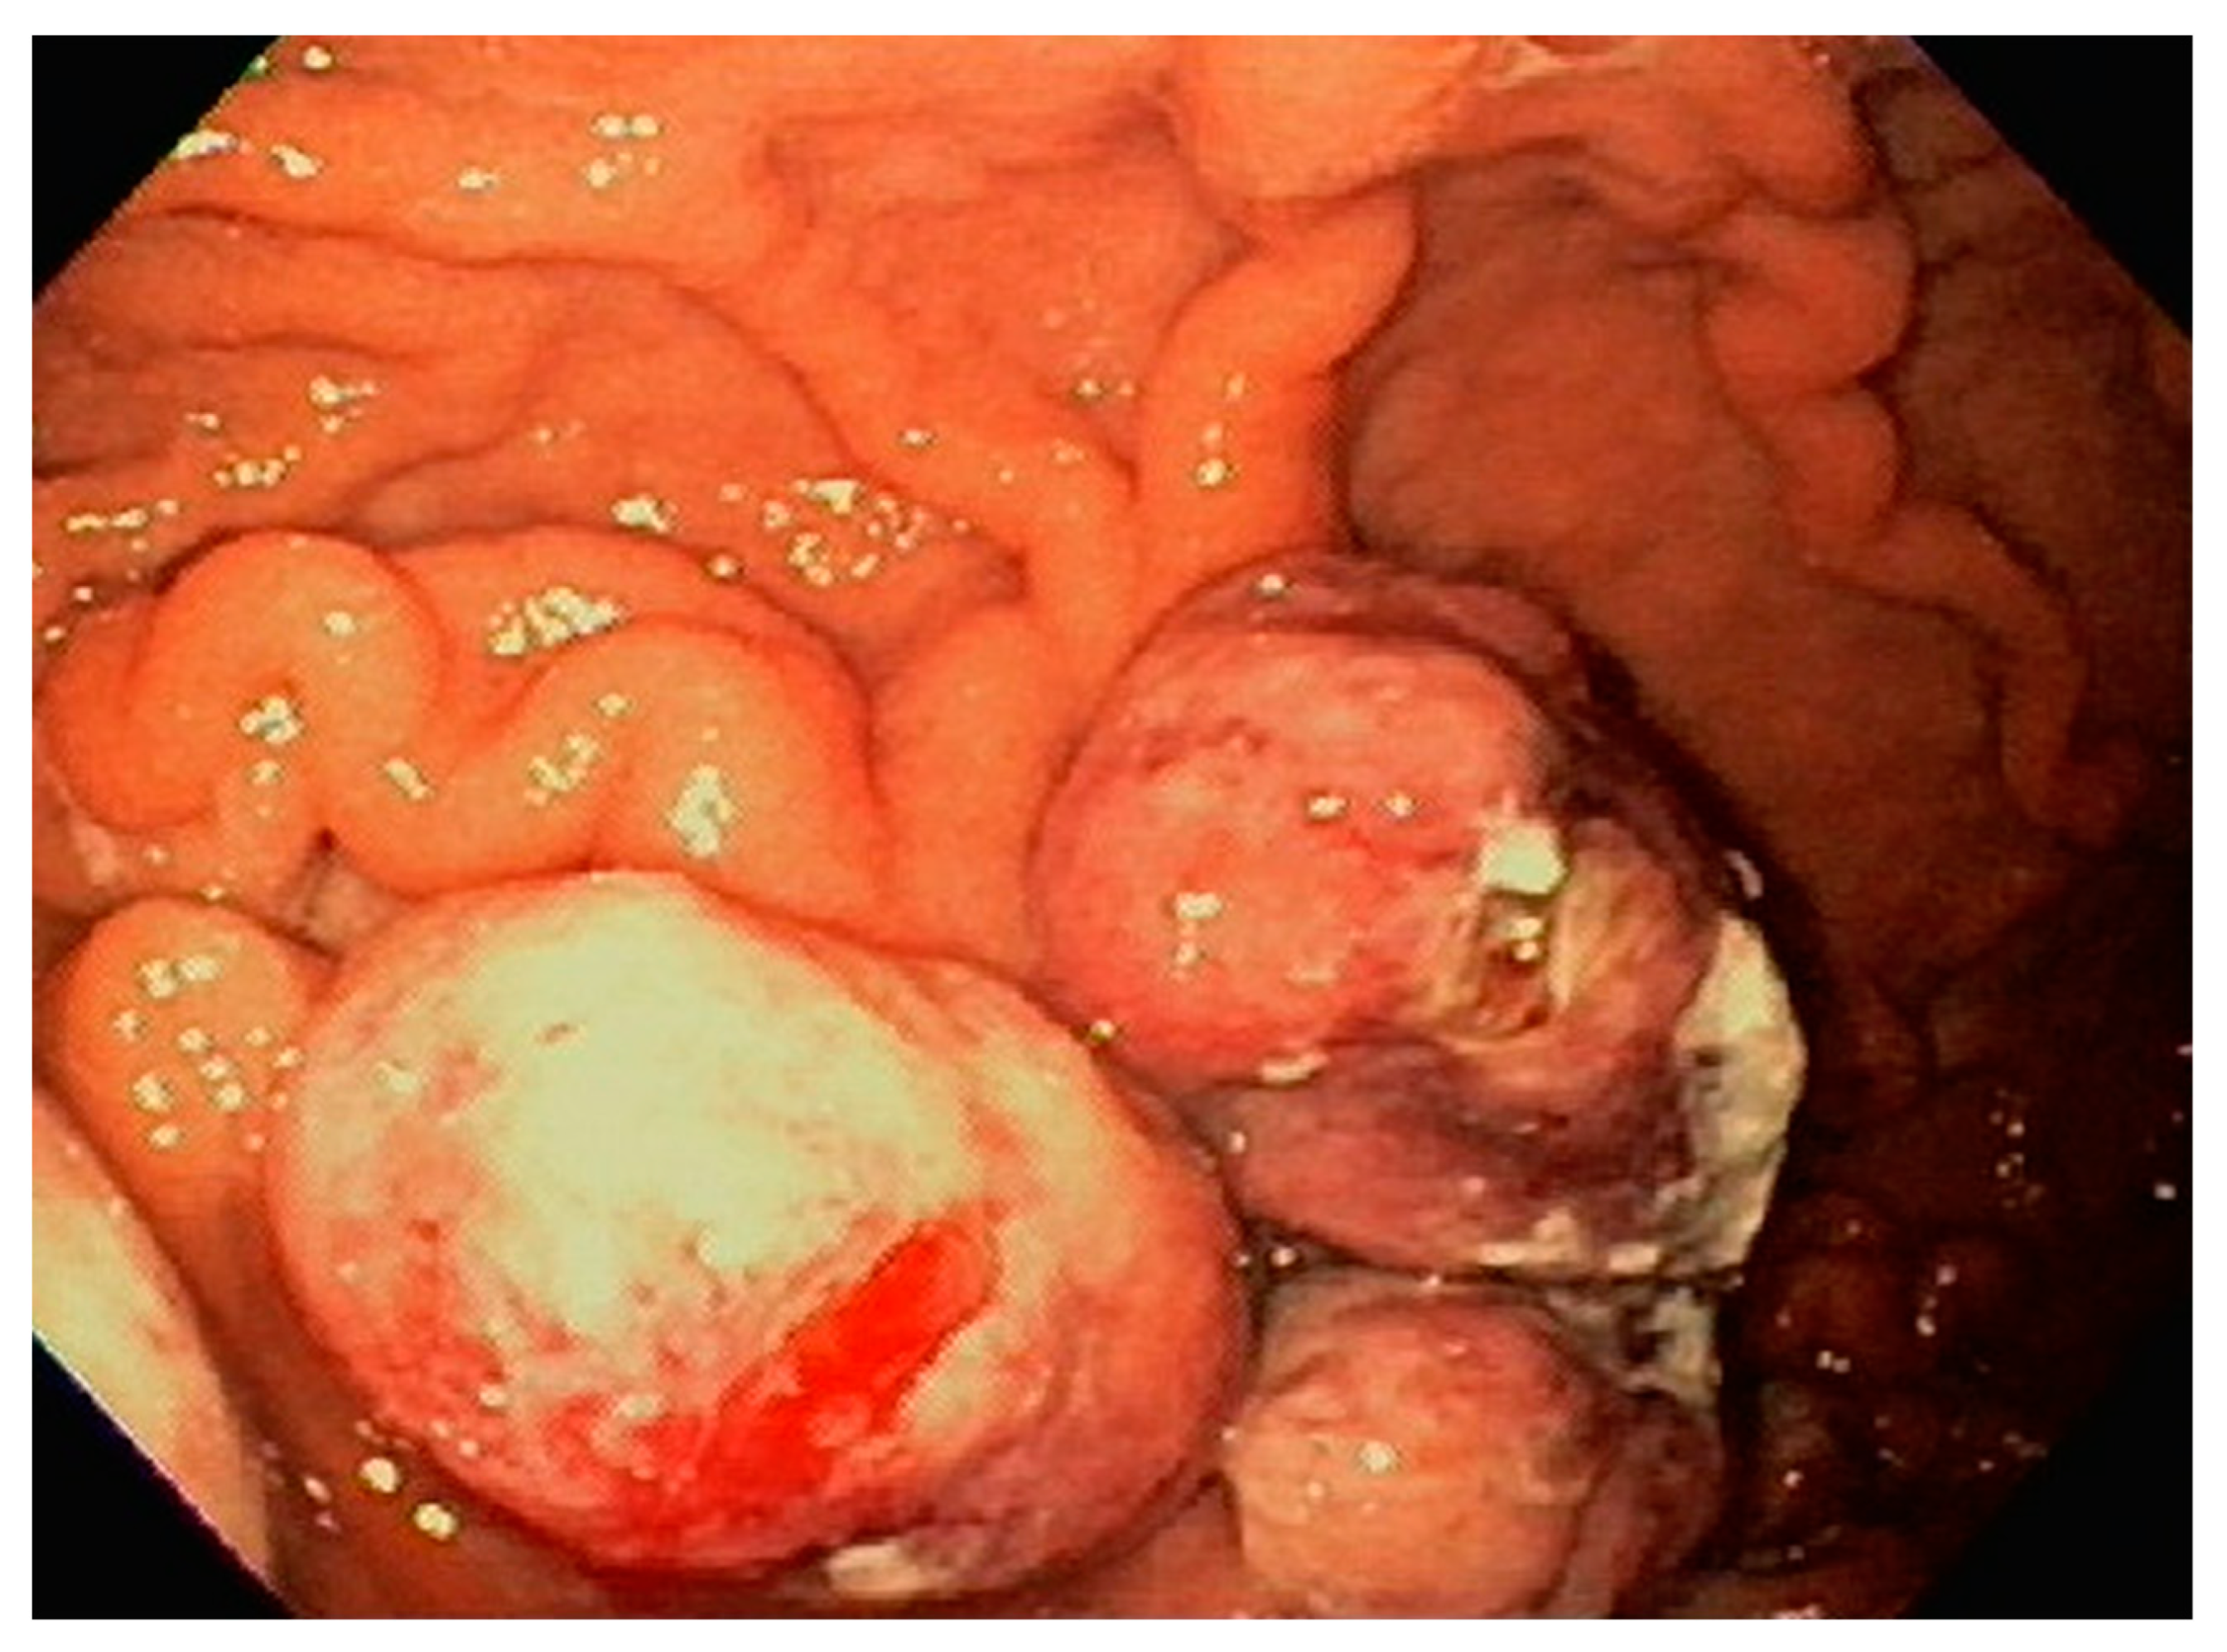

| 3 | F | 35 | Lung | Fundus | Fungating mass | Esophagus, mediastinum | Large-cell neuroendocrine carcinoma | Chemotherapy-carboplatin/ etoposide | Death 1 month after EGD diagnosis of metastasis |

| 4 | F | 73 | Kidney | Fundus and body | Multiple large friable masses | Liver and lungs | Clear cell renal carcinoma | Nephrectomy, chemotherapy, immunotherapy (Axitinib) | Death 10 days after EGD diagnosis of metastasis |